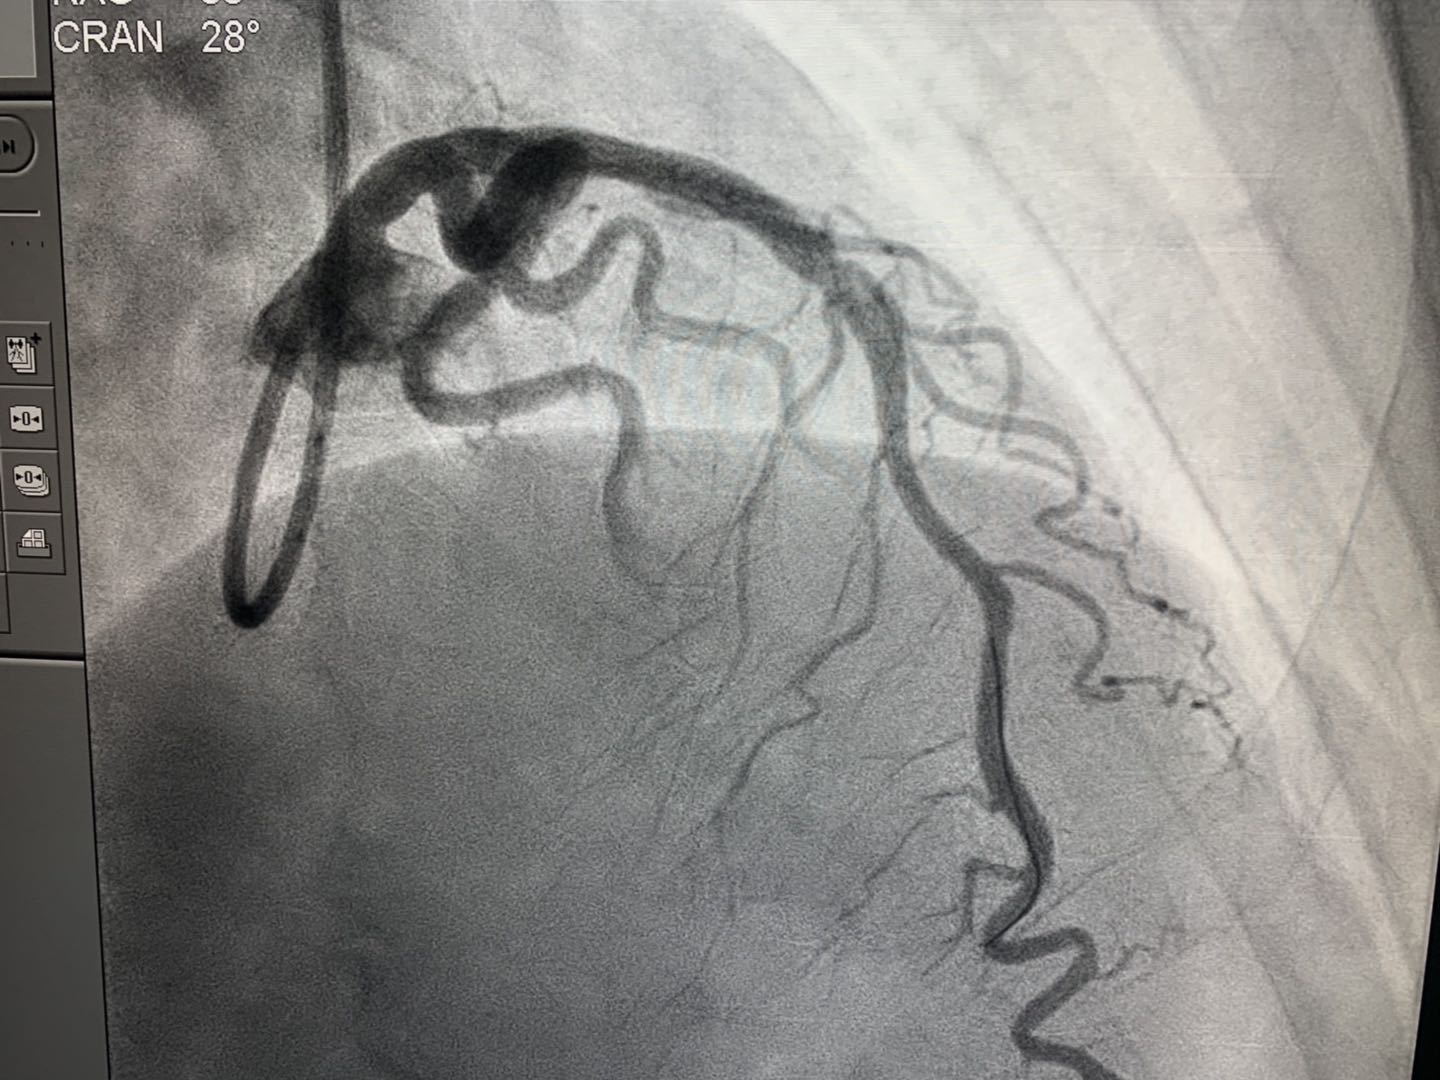

2019年4月16日,新疆首例生物可吸收心脏支架植入术在新疆医科大学附属中医医院(自治区中医医院)成功实施。医院心脏中心冠脉介入团队在武刚主任带领下,为一例50岁男性患者冠状动脉前降支近端成功植入NeoVas生物可吸收支架一枚。术中、术后采用光学相干断层扫描(OCT)对冠脉病变及植入支架进行评估。手术顺利,患者体征平稳。

专业擅长:擅长冠脉钙化病变的旋磨治疗,CTO病变介入治疗(冠脉慢性闭塞病变的正向、逆向介入治疗),FFR(冠脉压力导丝评定冠脉血流储备)指导冠脉支架精准运用予冠心病介入治疗。